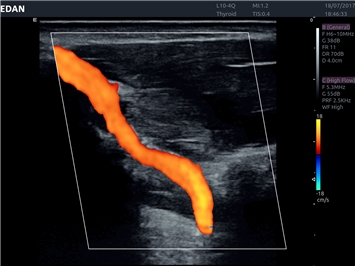

EDAN Acclarix LX4 представляет собой инновационную ультразвуковую систему, построенную на усовершенствованной платформе Acclarix. Сочетание высокого качества визуализации с интеллектуальным рабочим процессом делает эту систему оптимальным выбором для клиник, ценящих эффективность и экономичность.

• Сосудистой диагностики

• Автоматическое измерение толщины интима-медиа

Цветовой допплер:

Энергетический допплер: